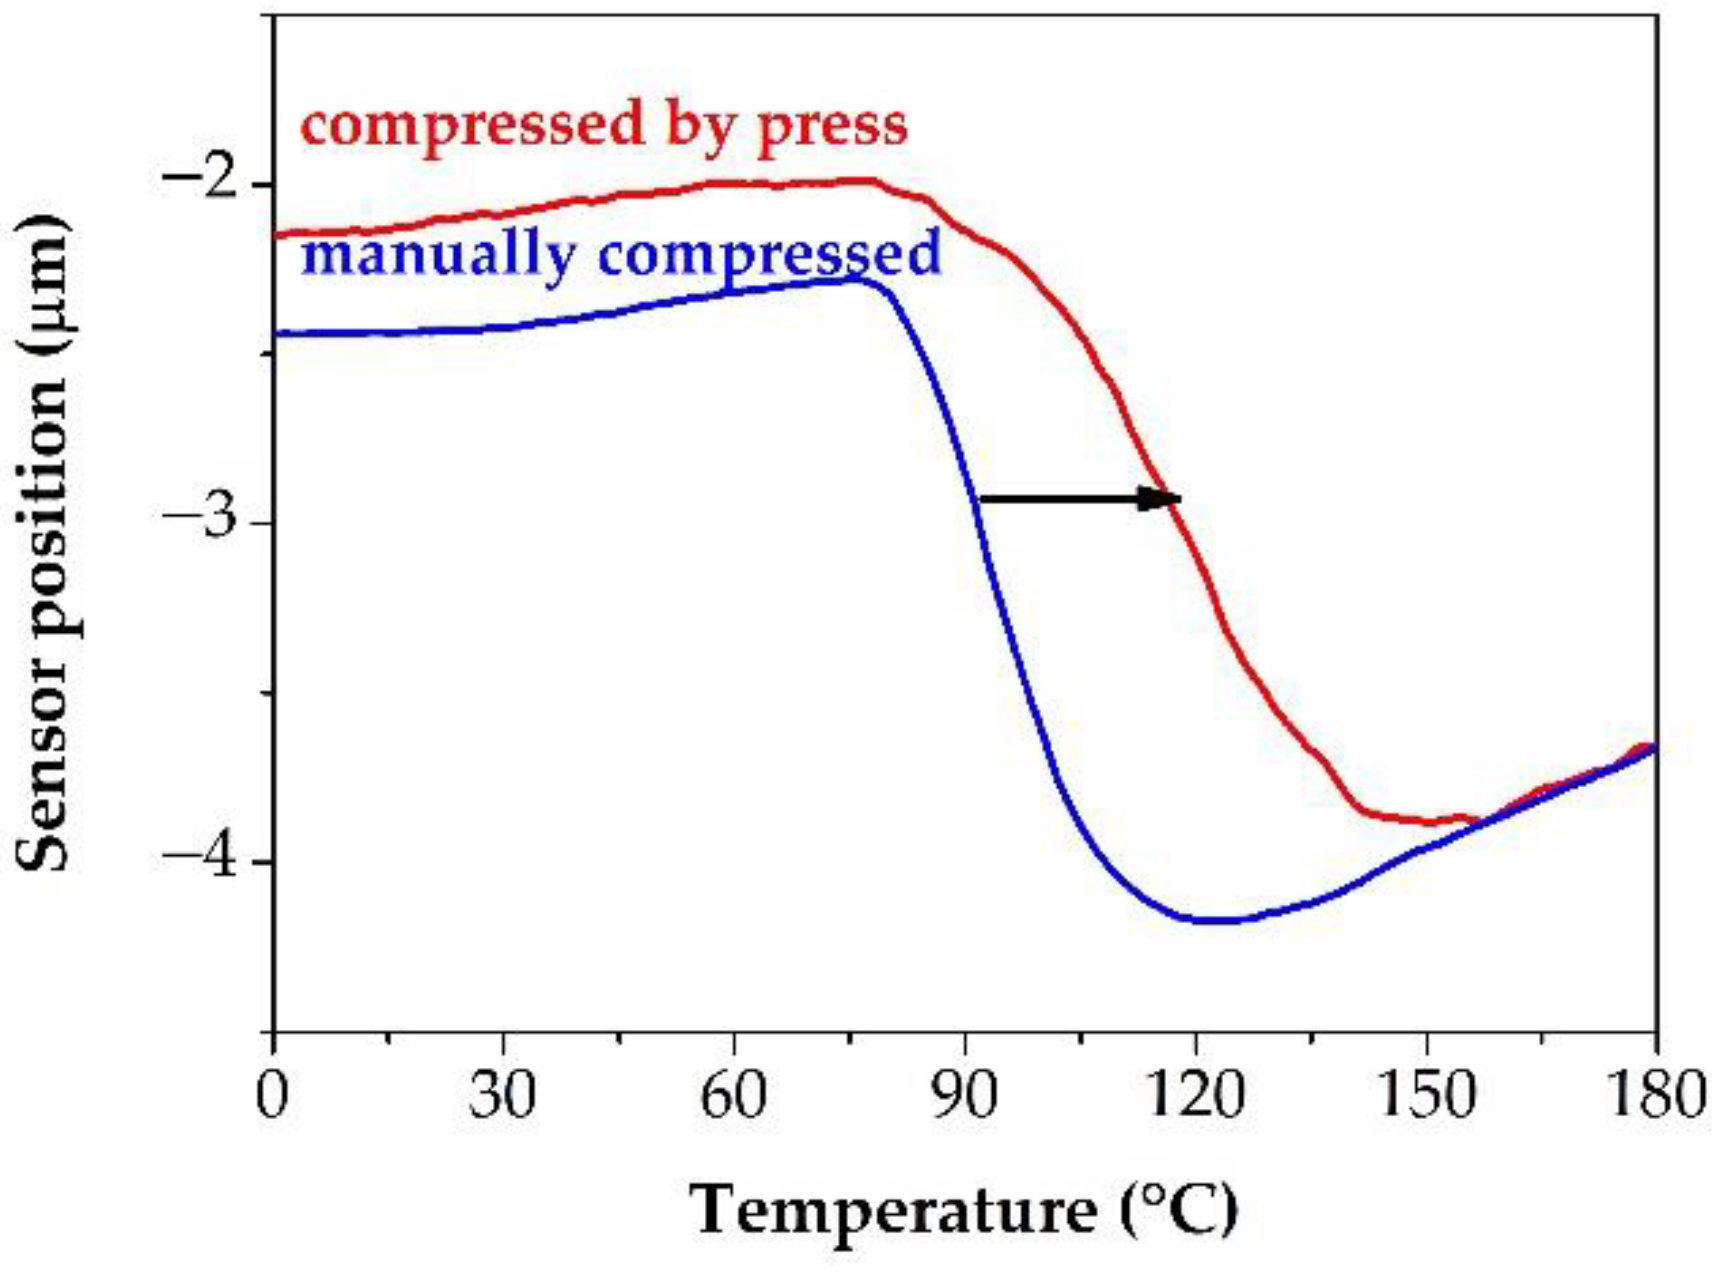

2.9. Stress Stability Test

3.2. Measuring the Glass Transition Temperature with Different Methods